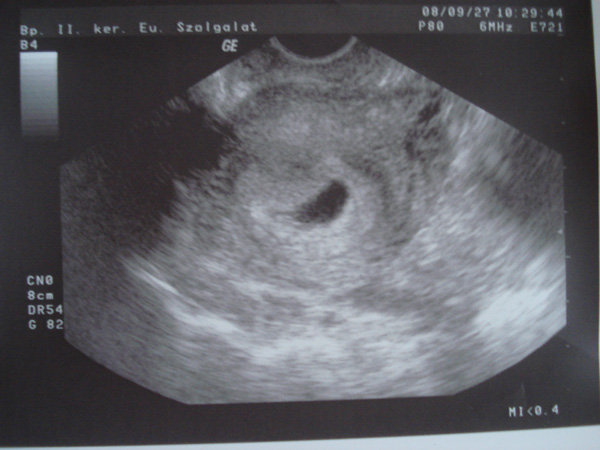

Nekem olyan, mint az örökkévalóság kivárni a hétfőt.. Pláne, hogy egy nagyon picit beszinezte valami a fehérneműm tegnap este, és olyan érzésem van, mintha meg akarna jönni. Ilyenkor emlékszik a szervezet a mensire, vagy feküdjek azért hétfőig? Ez nagon rossz jel? A 8- héten írtátok, hogy belefér a barnázás- Én most 6+3-n vagyok, és 46. napon, ilyenkor kellene jelezgetni a mesninek, amit eddig csinált, úgy 3 nappal az igazi előtt...